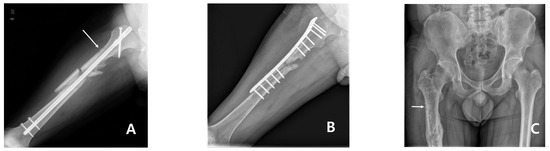

Subtrochanteric Insufficiency Fracture Occurring 5 Years after Surgery at the Steinmann Pin Insertion Site for Fracture Reduction